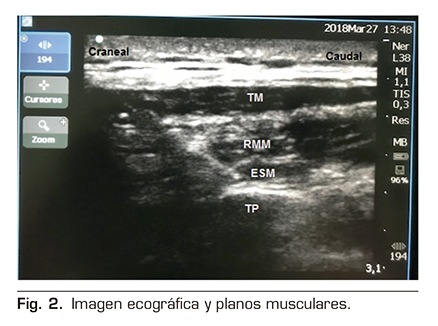

A la exploración física presentaba unas cifras de tensión arterial 150/90 mmHg, saturación arterial de O2 de 96 % al aire ambiente, murmullo vesicular conservado, no focalidad neurológica y dolor importante a la palpación de la pared costal izquierda. En los estudios de imagen realizados se evidenciaron múltiples fracturas costales en el hemitórax izquierdo, desde la 6.ª a la 9.ª costillas, sin evidencia de afectación pleuropulmonar aguda (Figura 1).